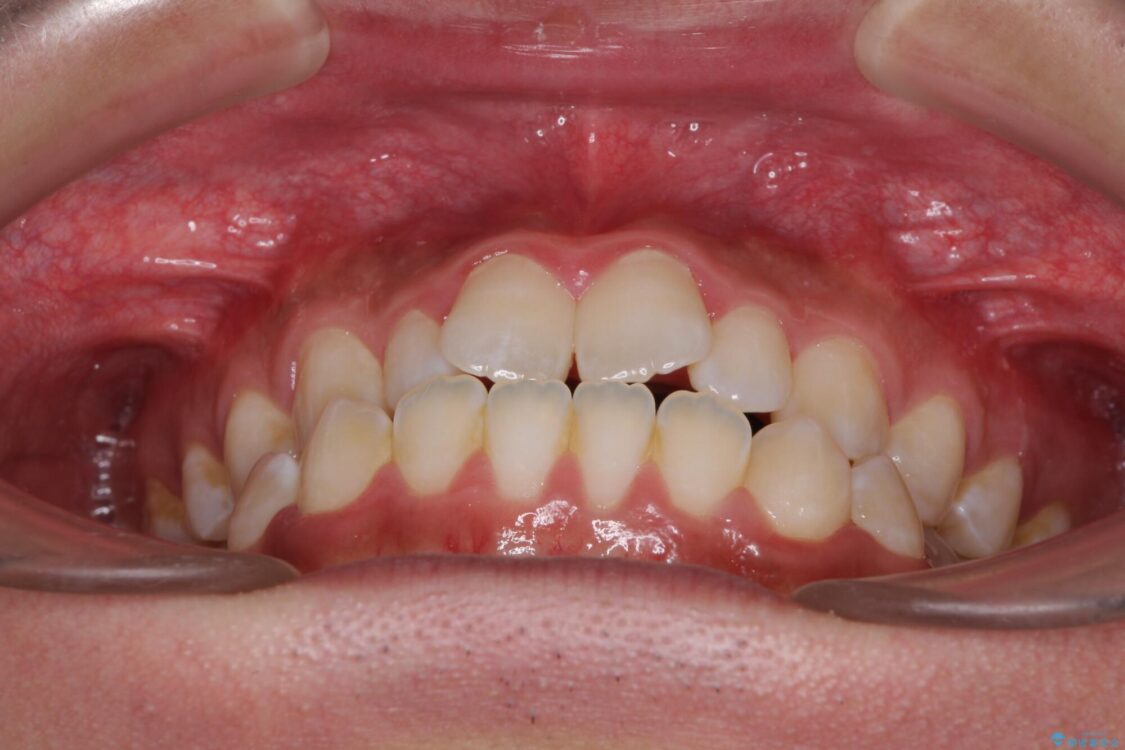

治療前

• 口元の突出感を改善 受け口傾向の咬み合わせの抜歯矯正 治療前画像

受け口傾向の咬み合わせと口元の突出感を気にして来院された患者様です。

受け口傾向特有の狭い上顎歯列であったため、歯列の拡大を補助装置で行い、下顎歯列全体を後方に移動させることとしました。

奥歯の咬み合わせを改善させた後、上下左右の小臼歯(下顎は残存乳歯)を計4本抜歯し、ワイヤー装置にて口元の突出感を改善しながら咬み合わせを整えることとしました。